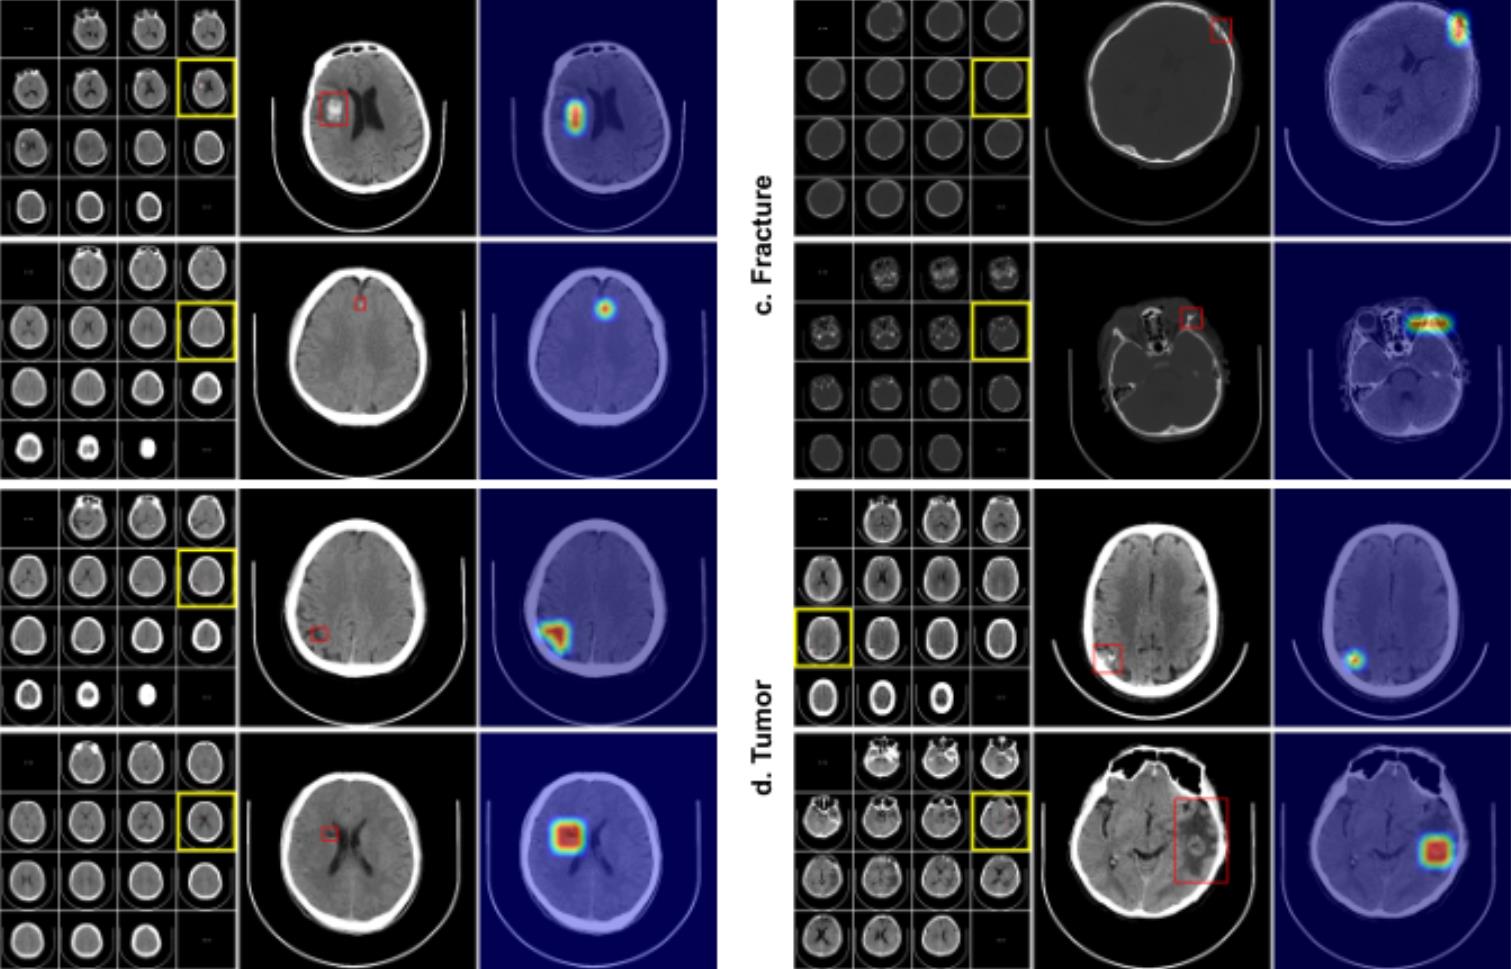

Tsinghua's Institute for Brain and Cognitive Sciences have helped create an AI that uses less man power to learn to detect a number of conditions linked to the head using computed tomography images. These conditions include stroke, brain haemorrhage (pictured), brain tumors and skull fractures.

The team used automatic keyword matching on the reports to generate labels for the scans, which they fed into their deep learning algorithm, RoLo (Robust Learning and Localized Lesion). This is called ‘weakly supervised’ machine learning, as it draws on disorganised and imprecise information to create training data. “Weak annotation can lead to wrong labels in training data and working at the scan-level labels means it does not show the specific location of relevant head lesions,” says Dai. “But it is much easier to create a large-scale training set this way, so we can shift the cost from expert labelling to novel AI algorithm design,” he says. Bigger data sets and better algorithms will help reduce the influence of errors, he adds.

To check whether their AI worked in a range of settings, Dai’s team tested it on about 3,000 CT scans taken from one hospital in China; 1,500 from several different hospitals; 1,500 from different scanning set-ups; and 500 from a dataset from India. They found their AI could correctly diagnose and distinguish between the four head disorders equally well across the different datasets. It averaged more than 96% accuracy, matching the performance of four radiologists who assessed the scans by eye.